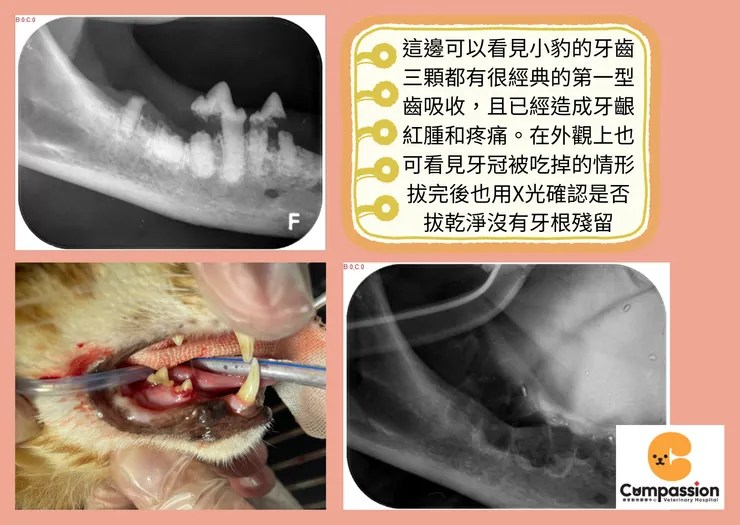

第一個案例是一隻有貓愛滋病史的8歲米克斯貓咪-小豹,因嘴巴味道加重開始改變飲食習慣而就診,經醫師門診檢查小豹身體狀況都很好,但是口腔檢查發現有嚴重牙齦紅腫的問題。之後安排全口腔檢查,麻醉下拍攝牙科X光發現小豹有嚴重多顆的齒吸收,小豹就是屬於經典的第一型齒吸收以及有一顆有第三型齒吸收狀況 (圖一),經過手術治療,之後的回診飼主表示食慾恢復很多、嘴巴也不會臭了 (ps.反而擔心會不會吃太胖)